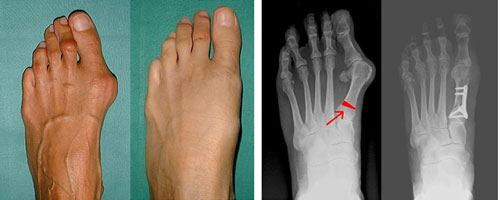

Hallux valgus - вальгусная деформация первого пальца стопы в плюснефаланговом суставе. Вследствие деформации палец отклоняется кнаружи под углом к остальным. Заболевание выявляется у женщин в 10 раз чаще, чем у мужчин. Предполагается, что причиной такой разницы является слабость связочного аппарата у представительниц слабого пола, а также ношение неудобной узкой обуви на высоких каблуках. Патология широко распространена и выявляется у лиц всех возрастов.

При визуальном осмотре стопа распластана. Выявляется видимая деформация и незначительная или умеренная гиперемия в проекции I плюснефалангового сустава. Первый палец отклонен кнаружи под углом к остальным. Пальпация безболезненна или нерезко болезненна, по внутренней поверхности стопы в области I плюснефалангового сустава определяется костный экзостоз и уплотнение кожи. Возможен небольшой локальный отек. Движения в I плюснефаланговом суставе, как правило, ограничены (степень ограничения движений может значительно варьироваться), при максимальном разгибании I пальца может возникать боль.

Диагноз Hallux valgus выставляется на основании симптомов и данных рентгенологического исследования. Выполняют рентгенографию I плюснефалангового сустава. Для более точной оценки патологии со стороны соседних анатомических структур при необходимости дополнительно назначают рентгенографию II и III плюснефаланговых суставов. Степень выраженности Hallux valgus определяется с учетом двух величин: угла между II и I плюсневыми костями (Intermetatarsal angle) и угла, под которым I палец отклонен по отношению к I плюсневой кости (Hallux valgus angle).

1 степень - угол между плюсневыми костями менее 12 градусов, угол отклонения I пальца менее 25 градусов.

2 степень - угол между плюсневыми костями менее 18 градусов, угол отклонения I пальца более 25 градусов.

3 степень - угол между плюсневыми костями более 18 градусов, угол отклонения I пальца более 35 градусов.

Наряду со степенью деформации при изучении рентгеновских снимков оценивают выраженность артрозных изменений. О наличии артроза свидетельствует сужение суставной щели, деформация суставной площадки, краевые разрастания и остеосклероз субхондральной зоны. В отдельных случаях для более точной оценки патологических изменений стопы пациента направляют на МРТ или КТ. МРТ стопы назначается для исследования состояния мягких тканей, КТ стопы - для изучения состояния костных структур. При заболеваниях, сопровождающихся нарушением нервной регуляции мышц, необходима консультация невролога.